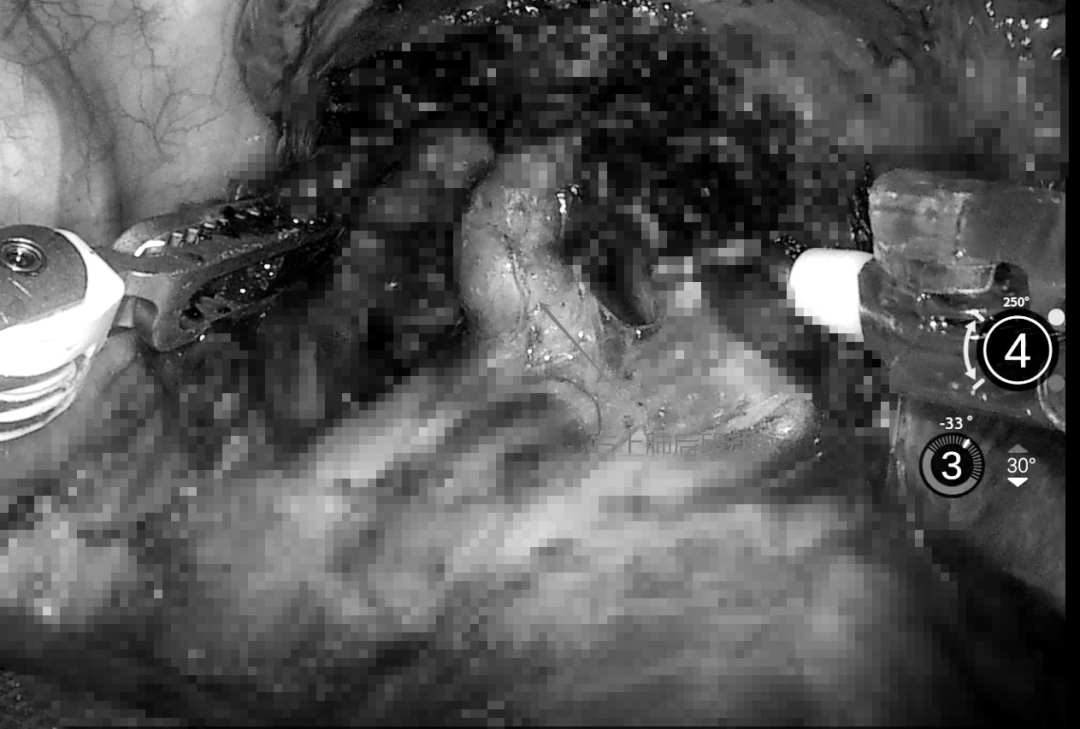

机械臂灵活地伸入胸腔,按照预设角度稳稳到达手术部位,与此同时,血管三维影像实时显示,精准锁定右上肺后段动脉,让手术团队能够清晰地观察到血管的走向和位置,从而确保术中血管离断精度达到亚毫米级。

机器人系统提供10倍放大三维成像,血管、支气管等细微结构纤毫毕现,尤其针对肺段解剖复杂的“血管三角区”(如后段动脉分支),可规避传统手术中因视野受限导致的误损伤。

机械臂可模拟人类手腕7个自由度运动,在狭小胸腔内完成360°无死角操作。反向角度绕过重要组织,实现“非接触式”病灶切除,降低术后并发症风险。